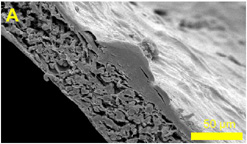

|  |  | Skin cells growing on a polymer scaffold ...

© University of Sheffield

| Tissue Engineering

Scientists are turning to chemistry and engineering to develop a range of artificial skin and bone which can be used to improve the treatment of burns and bone diseases.

Tissues are being grown by using complex man made 'scaffolds' to support them – not unlike scaffolding on a house - these scaffolds are not made from steel but of bio-ceramics and plastic polymers.